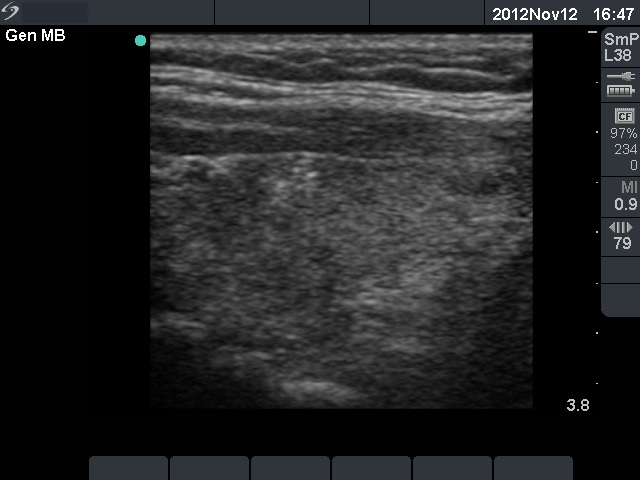

First examination (1st and 2nd rows of images):

Ultrasonography: there were multiple hypoechogenic areas with blurred borders within echonormal background. The vascularization was decreased.